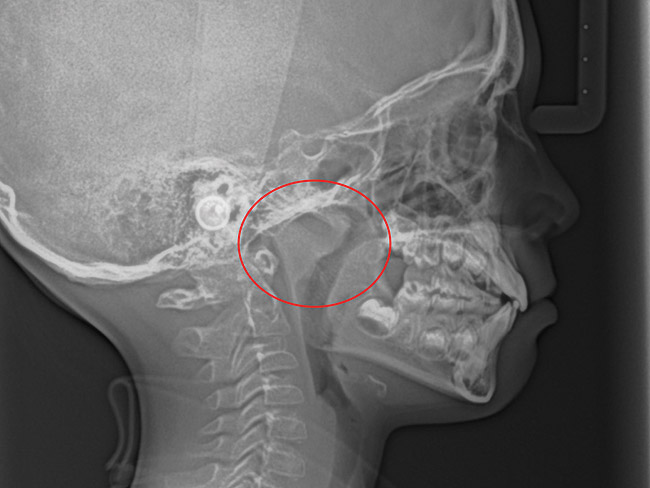

(11.) Adenoidal tissue blocking the velopharyngeal airway.

Figure 11

Tonsils and adenoids should be judged against the relative size of the airway rather than the absolute size of the lymphoid tissue46 (Figure 5 and Figure 6). Adenoids are located at the posterior of the nasal cavity on the roof of the nasopharynx (Figure 7). The normal distance from the adenoids to the soft palate for an acceptable airway should be at least 12 mm. For each millimeter decrease, the odds of the child snoring increase 1.61 times. Mouth breathers typically show a smaller upper airway dimension as well.47 The adenoid and tonsillar obstruction creates the trigger, but the deviate facial and neck muscle recruitment and tongue hypotonia cause the maldevelopment.48

The point of obstruction tends to determine the type of skeletal impact. Nasal obstruction from enlarged turbinates, blocked ostium maxillare, deviated septum, or nasal valve stenosis creates Angle occlusions of Class I, II, and III equally (Figure 8). The maxilla in these cases is positioned posteriorly and the mandible is posterior-inferior. The facial type is most commonly dolicocephalic. Blockage of the airway predominately by the adenoids will create growth patterns that yield mostly Class II occlusions and anterior open bite with both jaws located posterior-inferiorly. Facial type is again dolicocephalic with the typical long-thin “adenoidal” face49 (Figure 9 through Figure 12). If the tonsillar tissue is responsible for the airway obstruction, the tongue will have an abnormal resting posture. Class III occlusions will be more common with the maxilla normal or posterior placed (Figure 13 through 15). The tongue may direct the mandible anteriorly or, because the tongue is not in the roof of the mouth driving A point anterior, the maxilla will become bimaxillary retrusive.50 In some cases, the anterior posture of the tongue will create an open bite. This is incorrectly referred to as a tongue thrust. The impact from a thrust does not alter the tooth position. Long-term, low forces cause tooth movement. The posture of the tongue against or between the anterior teeth due to the excessive tonsillar size creates the open bite (Figure 16 and Figure 17). Facial types in this group are more brachyfacial. Lastly, if the airway is blocked through a combination of factors, the Angle classification will be either Class II or III. The maxilla will be in a normal location and the mandible will be the affected arch (Figure 18). These craniofacial changes are not restricted to OSA; all SDB will create unique alterations depending on the patient compensation. Children with UARS have been reported to display high, narrow palates, dolicofacial form, and a Class II malocclusion, indicative of largely adenoidal blockage.51